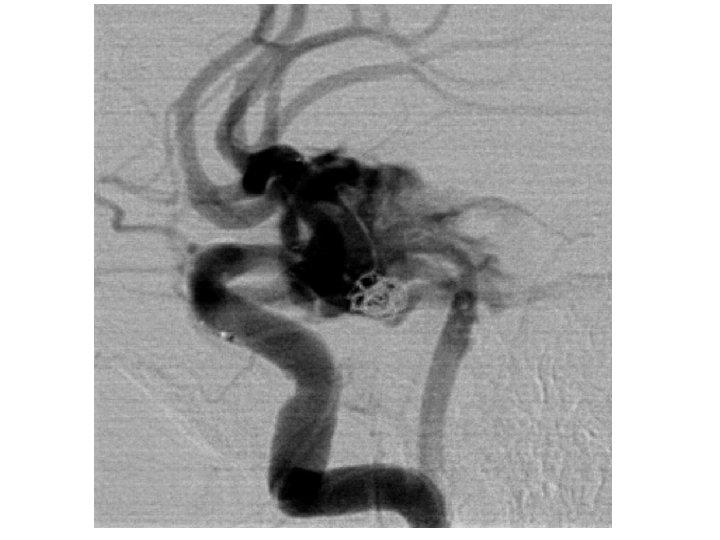

Clinical Presentation “Worst headache of my life”--80% Sentinel bleed— 10% AMS, vomiting, seizures, stiff neck, focal deficits Diagnosis: CT scan, if negative LP If positive, then either CTA, MRA, or angiography to spot the lesion